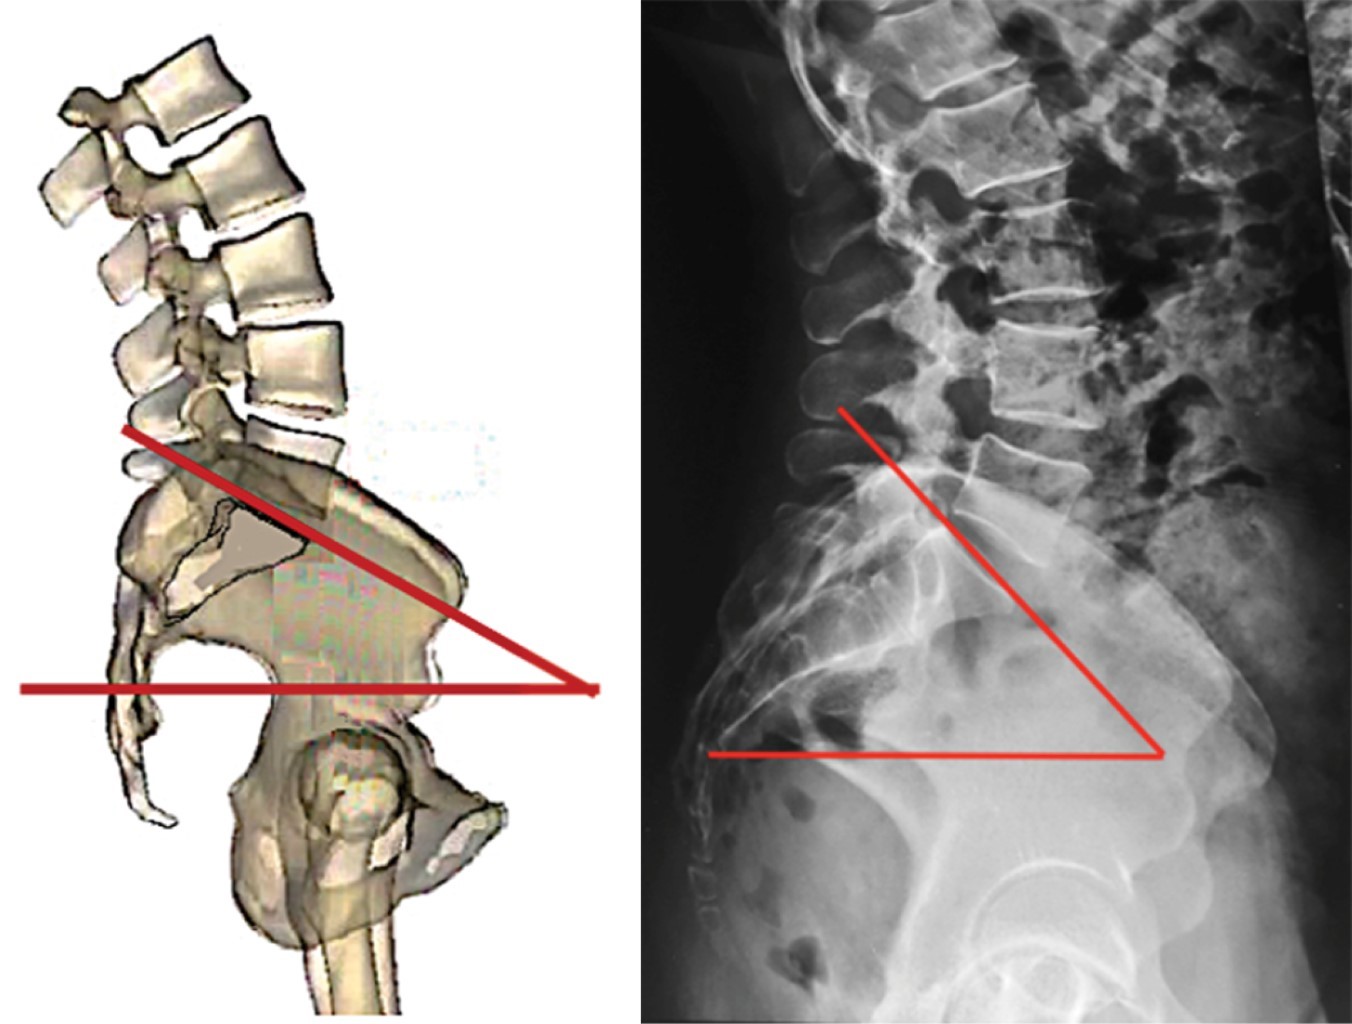

Pendiente sacra (ángulo de Ferguson). Es el ángulo que se forma entre el eje transversal y una línea paralela a la plataforma sacra. Un sacro verticalizado tiene un ángulo con valor bajo, un sacro horizontalizado tiene un valor alto (Figura 12). Los valores promedio en mexicanos sanos son de 35.6° ± 7.8° en bipedestación y de 36.5° ± 7.9° en decúbito.33

El ángulo de pendiente sacra permite determinar la magnitud de la lordosis lumbar ya que éste determina la magnitud de su curvatura; es decir, a menor pendiente, menor lordosis y a mayor pendiente mayor lordosis. Observe en la Figura 13 los efectos de la pendiente sacra en la magnitud de la lordosis lumbar.

Figura 13